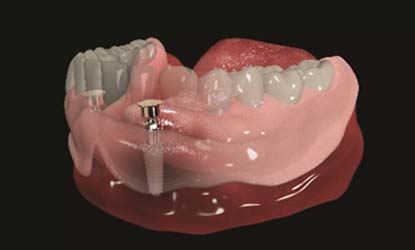

Problema: Nepakankamas kaulo aukštis dantų implantui

Tikslas:

Pakeisti trūkstamą dantį dantų implantu per vieną kartą

Rezultatas:

Atlikta sinuso elevacijos procedūra ir dėka gero pirminio stabilumo vienmomentiškai įsriegti dantų implantai